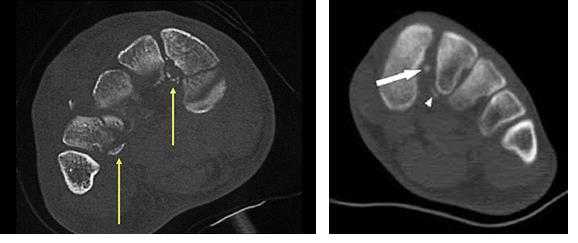

2. КТ при переломовывихе сустава Лисфранка:

• Позволяет обнаружить переломы, не выявленные при рентгенографии

о КТ позволяет оценить тяжесть травмы

о Аксиальные срезы должны проходить параллельно оси плюсневых костей

о В сагиттальной плоскости визуализируется смещение костей в тыльную сторону

о В коронарной плоскости лучше всего видны переломы клиновидных костей

4. КТ при повреждении связки Лисфранка:

• Поскольку при КТ исследование с нагрузкой не проводят, смещение плюсневой кости может визуализироваться хуже, чем при рентгенографии

Компьютерная томография (КТ). Этот метод исследования отличается гораздо более высокой по сравнению с рентгенографией диагностической ценностью и позволяет получить изображения поперечных срезов костей стопы. Для диагностики повреждений сустава Лисфранка он также обычно не требуется, однако он может назначается при предоперационном планирования для точной оценки характера повреждения и уточнения числа поврежденных костей и суставов стопы.

В сложных с диагностической точки зрения случаях целесообразно использование КТ и МРТ.